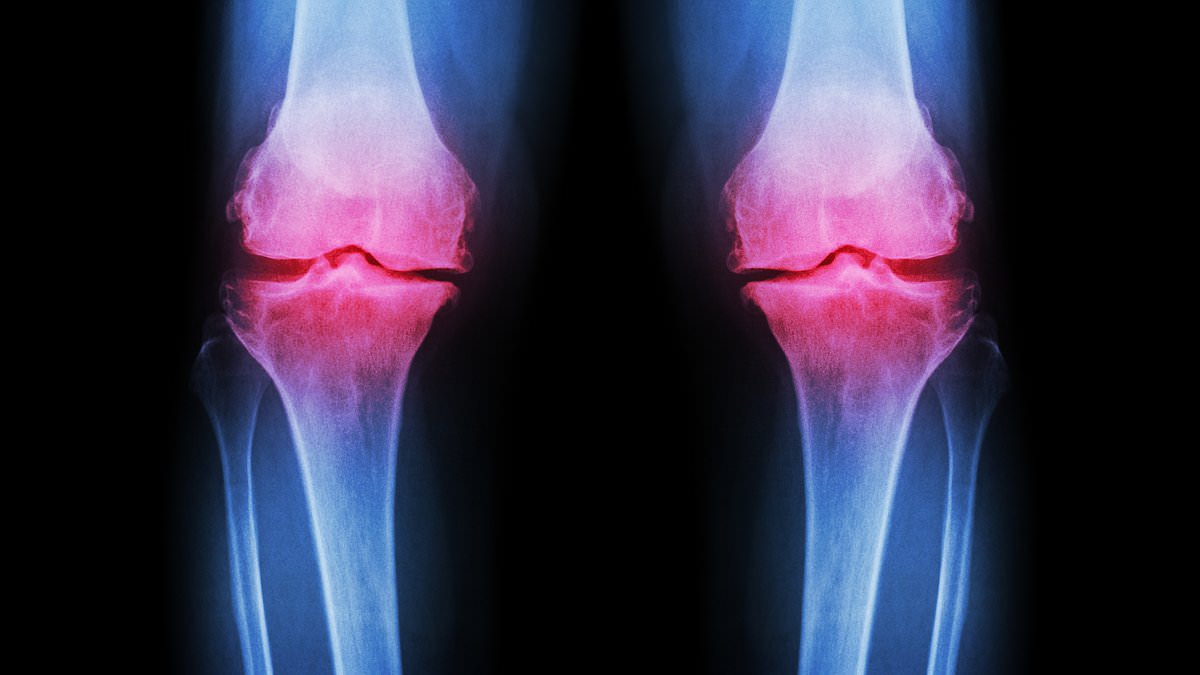

Osteoarthritis occurs when cartilage—the protective tissue between bones—breaks down, causing bones to rub together and joints to swell. Normal joint wear and tear is typically repaired by the body, but excessive strain from repetitive exercise or improper nutrition can overwhelm this process. Post-traumatic osteoarthritis, often linked to fractures in joints like the ankle or knee, is becoming more common among young athletes. 'Improper healing from injuries alters joint mechanics, accelerating cartilage degradation,' explained Sinnett. This condition, which usually appears after 45, is now affecting people as young as 25.